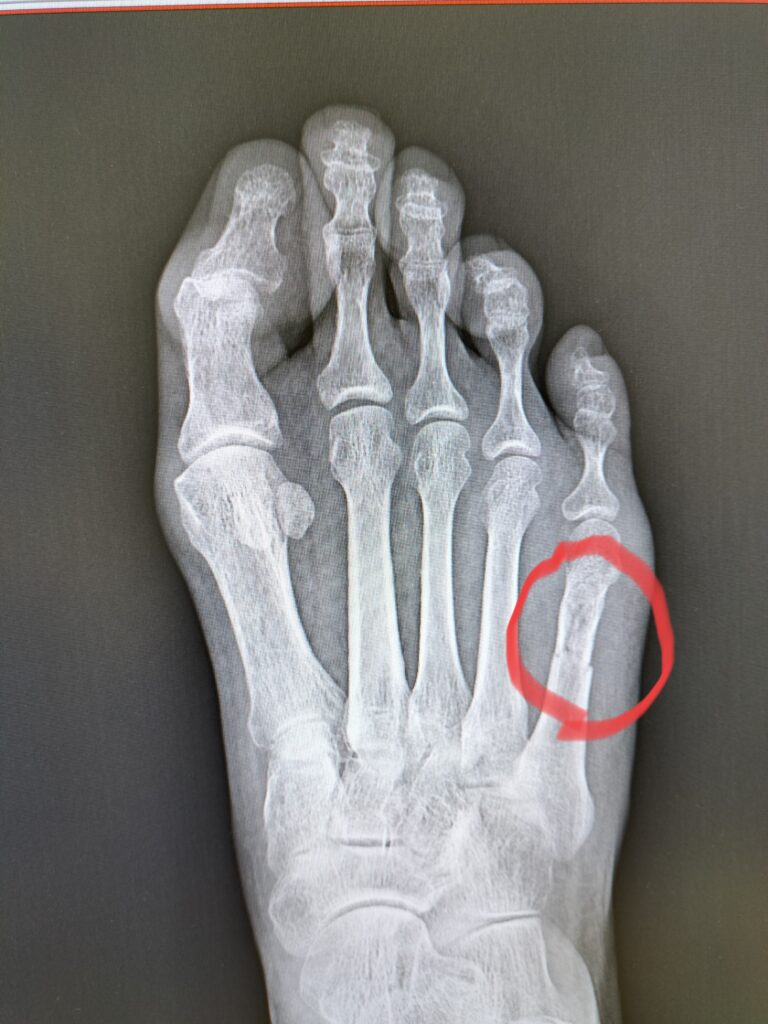

お医者さんでレントゲンを撮った。診察室に入るよう呼ばれたら、レントゲン写真が出ている。

あ!折れてる😱

素人の私でも分かったわ😭

先生が来て、「折れてますね。結構重症です」と